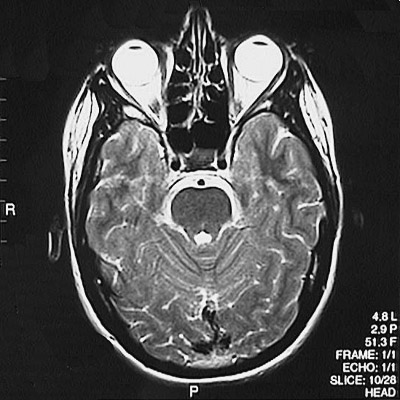

This is a normal axial T2 weighted MRI scan demonstrating the temporal lobe and occipital lobe and basilar artery and internal carotid artery and basis pontis and aqueduct of Sylvius and cerebellar vermis and ethmoid sinus and pituitary and globe of eye and lens of eye.